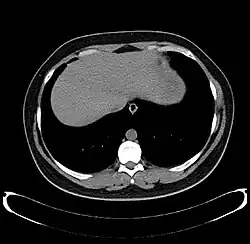

The diagnosis of liver disease is made by liver function tests, groups of blood tests, that can readily show the extent of liver damage. If infection is suspected, then other serological tests will be carried out. A physical examination of the liver can only reveal its size and any tenderness, and some form of imaging such as an ultrasound or CT scan may also be needed.

-

Axial CT image showing anomalous hepatic veins coursing on the liver's subcapsular anterior surface[74] -

Maximum intensity projection (MIP) CT image as viewed anteriorly showing the anomalous hepatic veins coursing on the anterior surface of the liver -

Lateral MIP view in the same patient as previous image -

A CT scan in which the liver and portal vein are shown